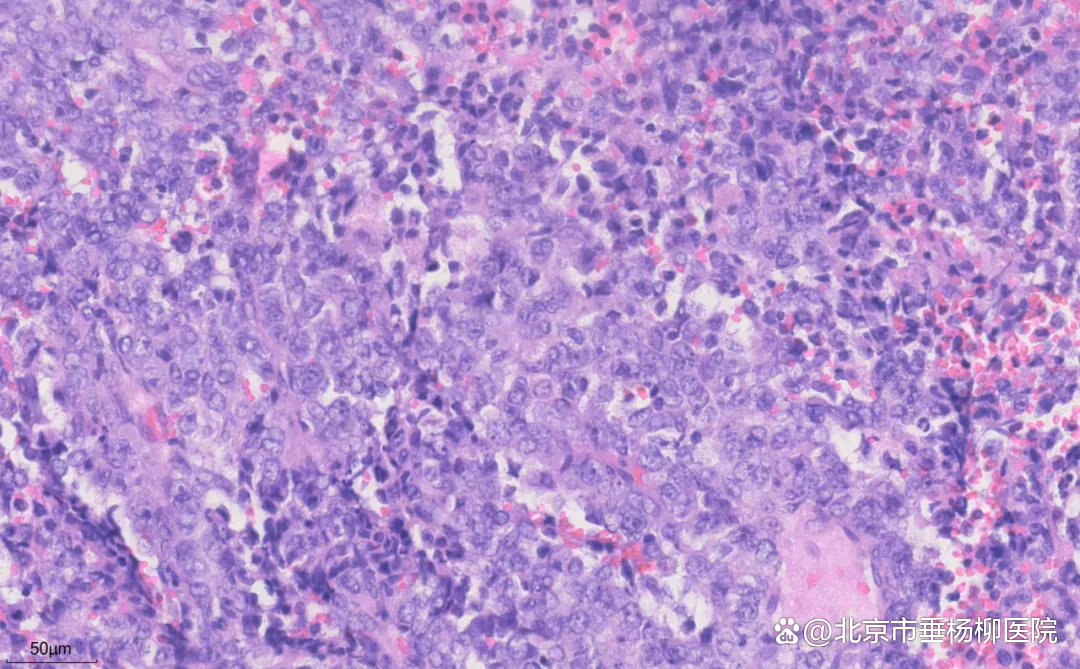

细胞沉渣石蜡包埋HE切片:血性背景中可见大量恶性肿瘤细胞,粘附性差,核形不规则,可见泡状核,部分胞浆丰富,核分裂象易见。